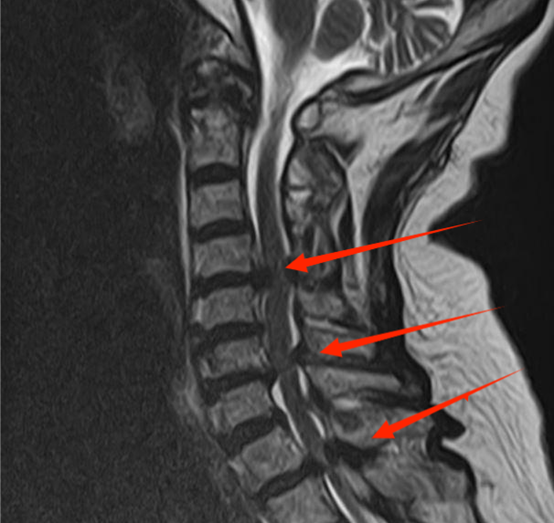

▲图为术前椎管内受压情况